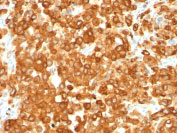

Formalin-fixed, paraffin-embedded human Melanoma stained with gp100 / Melanosome Monoclonal Antibody (HMB45).